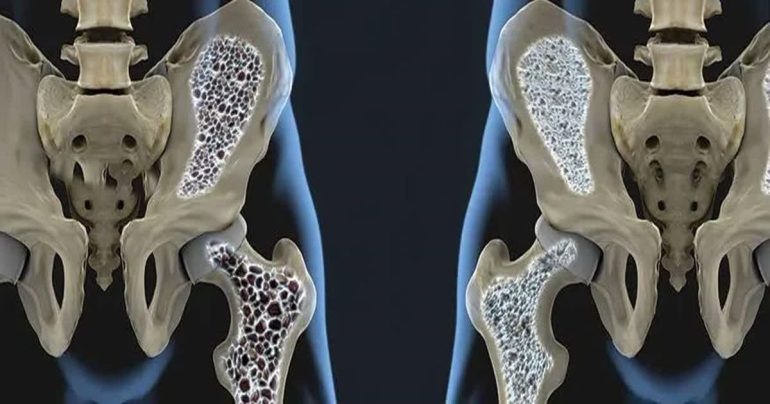

تراکم استخوان

سنجش تراکم استخوان (BMD)

Dual energy X-ray Absorptiometry (DXA) مؤثرترین روش برای تخمین ریسک شکستگی در خانمهای یائسه است و در سنجش تراکم استخوان، استاندارد طلایی محسوب میشود.

اندازهگیری تراکم استخوان معمولاً با دستگاه DXA و در دو ناحیه مهرههای کمری و هیپ انجام میشود.